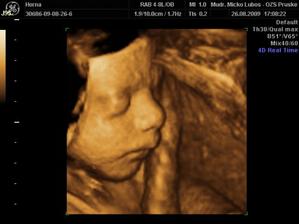

Náš novembrový darček

Na našom drobčekovi sme začali s drahým pracovať v januári. Posledné lieky som vysadila po Silvestri 2008 a vo februári sme splodili náš malý pokladík. Ani som neverila, že to pôjde tak rýchlo. Strašne sa obidvaja tešíme na malého a celé tehotenstvo je pre mňa jeden veľký zázrak.

Našťastie som nemala žiadne komplikácie akurát teraz ku koncu už mi tvrdne bruško. Tak musíme papať lieky a veľa veľa oddychovať. Náš termín 14.11. sa blíži tak sa snažím v kľude študovať múdru literatúru a pomaly sa pripravujem na môj prvý pôrod 🙂)